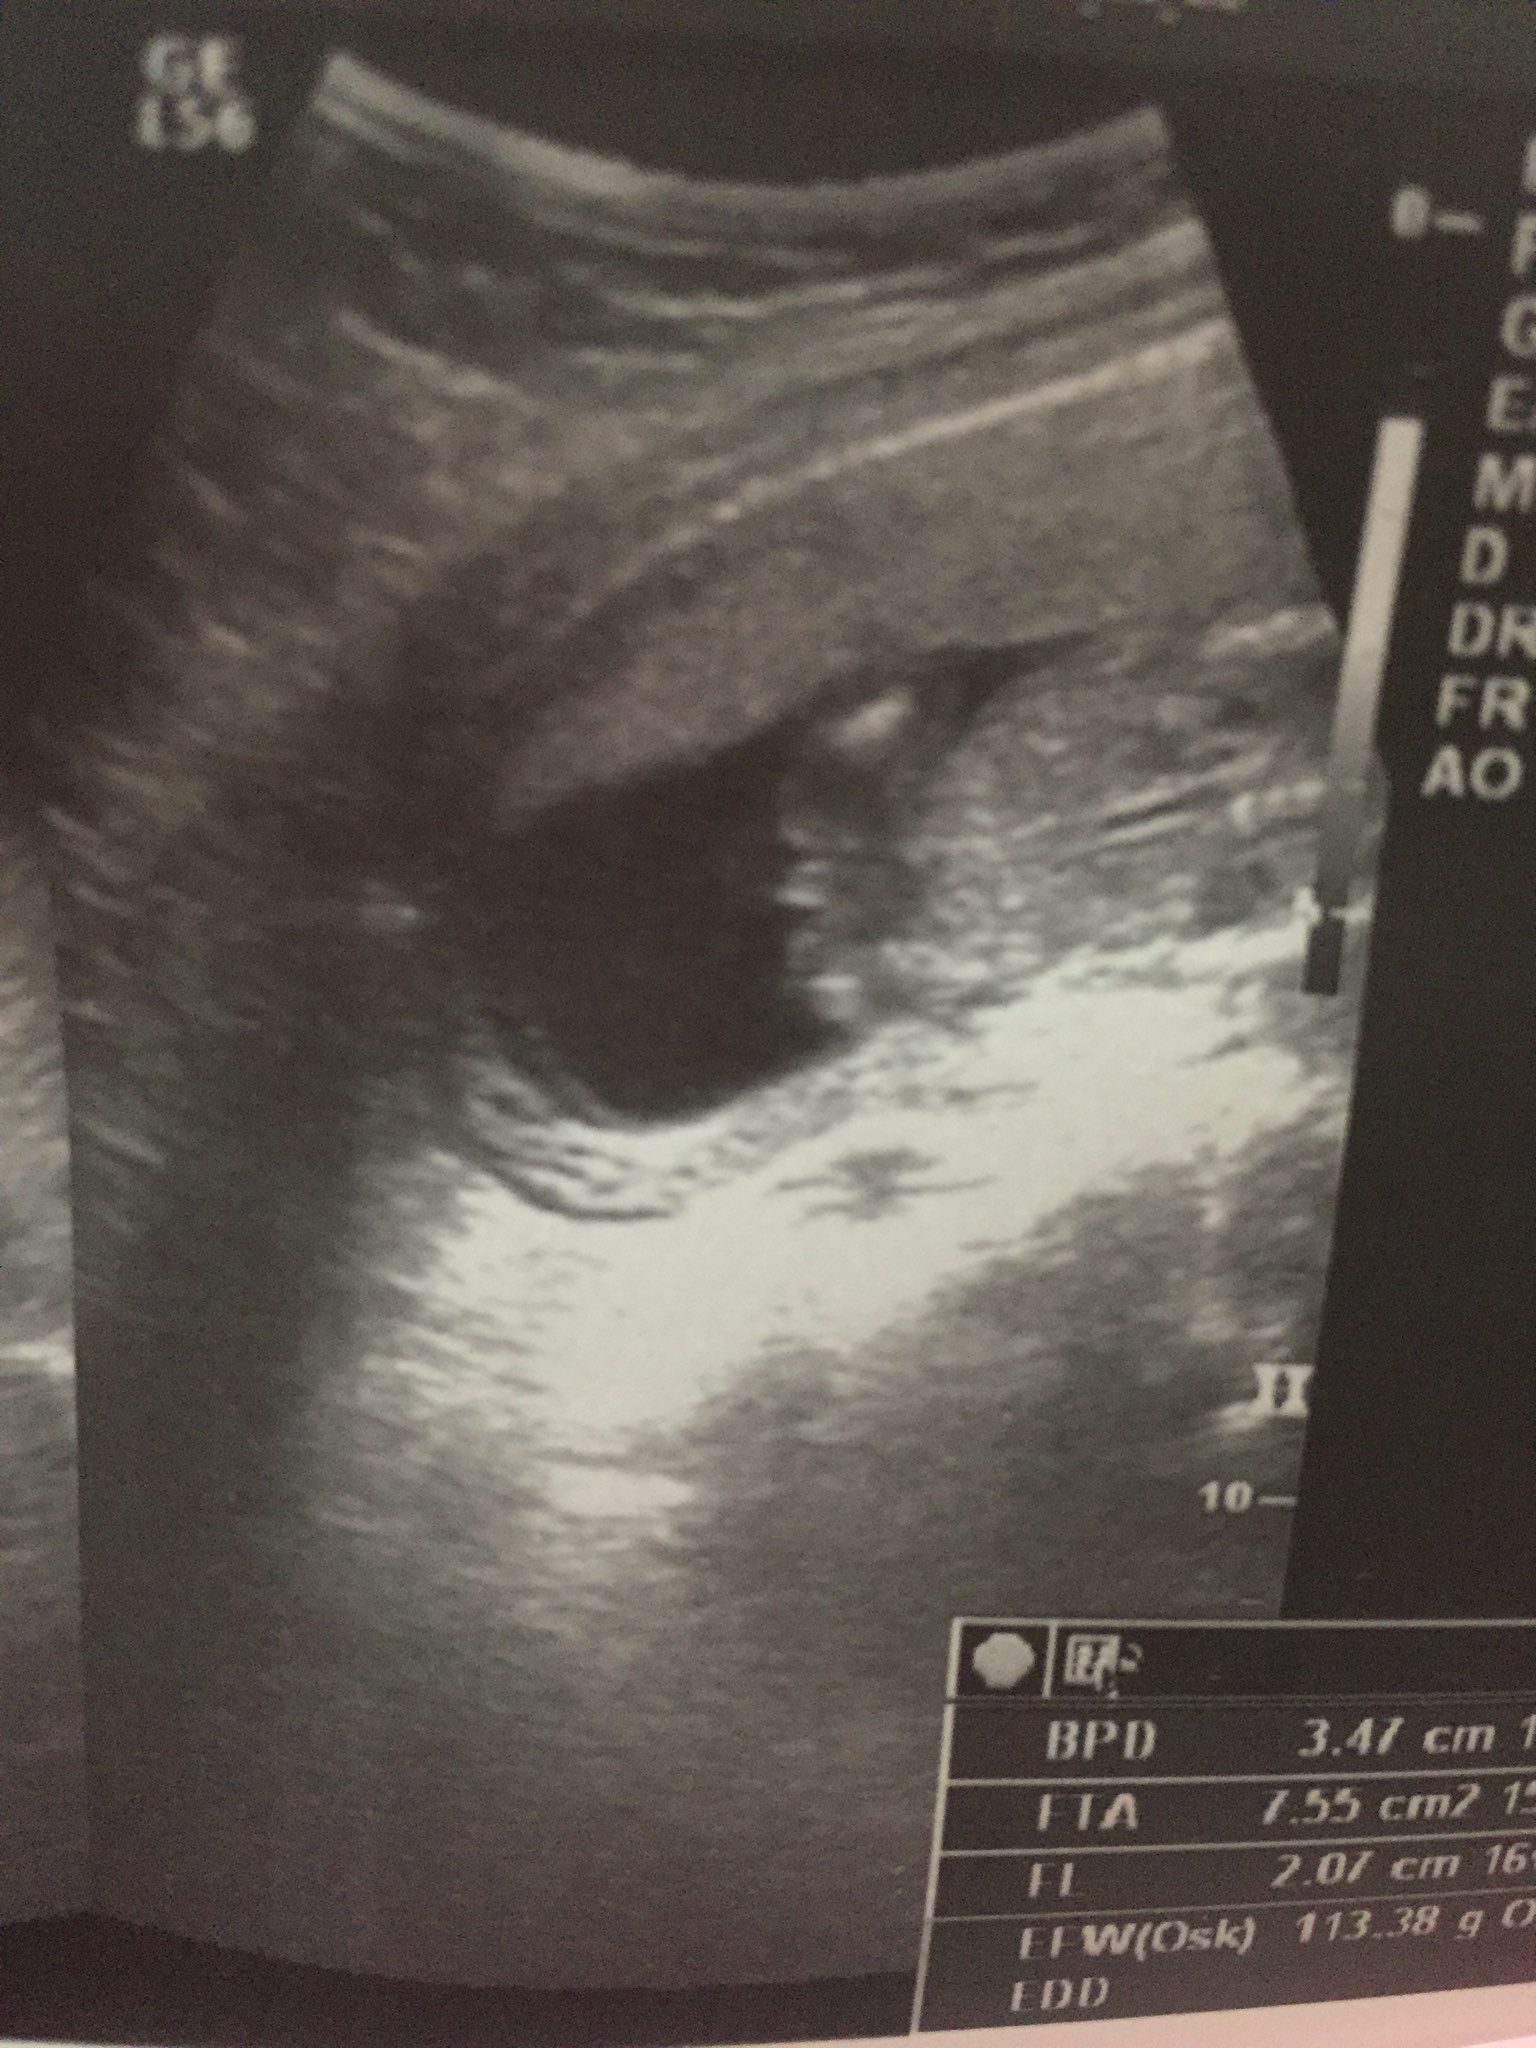

看的出來有三條線還是白點嗎?目前16w2d(男還女)